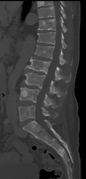

Pathological fracture of the lumbar spine due to multiple myeloma